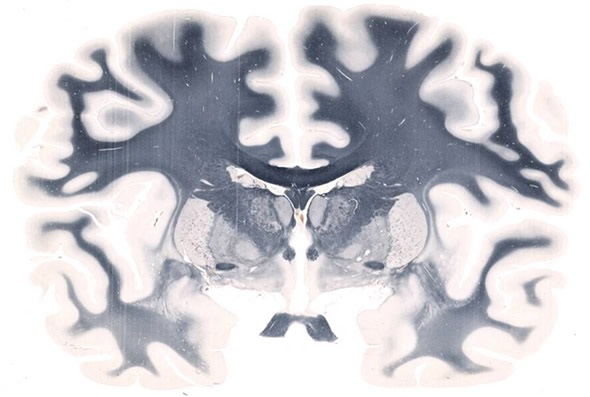

Whole Mount Brain - 5

Whole Mount Brain - 5" x 7" at 20X. Image credit: Huron Digital Pathology.

Typically, a brain section might by 5 by 7 inches, for example. That's our standard scanner, but we also have its older brother, the LE 120, which is able to load 10 slide holders so that you're scanning 10 brain sections automatically, without intervention.